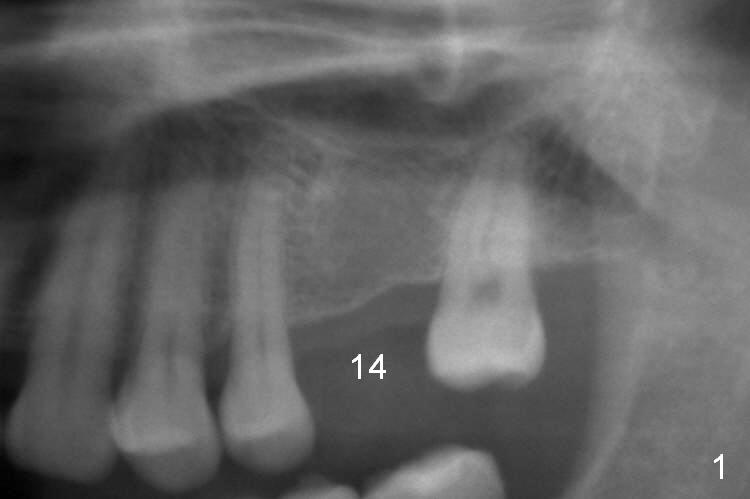

A 49-year-old man is an engineer. The tooth #14 is missing (Fig.1,2). He wonders how a one-rooted implant can replace a three-rooted tooth. Anyway, osteotomy is initiated at the site with 2.5 mm reamer in place (Fig.3). A 5x8 mm Bicon implant is placed (Fig.4). Seven and a half months later, the bone density next to the implant plateau appears to increase (Fig.5 arrowheads, as compared to Fig.4). The beauty of Bicon implant is that the crown (Fig.6 C) can be extraorally cemented to the abutment (A) prior to re-seating. Two years and 3 months post cementation, while no residual cement is visible, the bone density at the crest has increased (Fig.7 arrowheads). The crown is de-cemented 4 years 4 months post cementation; it appears that the abutment is small and short (5x2 mm 10 degree stealth). The bone density of the cortex around the implant (Fig.9 ^) is higher than that at #15 and #3.